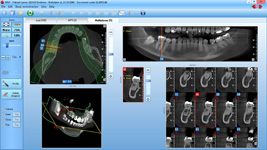

• Řízená implantace - guided surgery – statická navigace

- operace pomocí OP šablon. Ve speciálním programu coDiagnostiX se využívají data z CB CT scanu - tedy údaje o množství a kvalitě kosti, dále data získaná ze scanu modelu čelistí s modelem plánované protetické náhrady (korunky, můstku…)

- tedy údaje tloušťce sliznice, pozice a tvaru náhrady.

Tím máme všechny potřebné údaje pro plánování pozic implantátů, jejich potřebné délce a průměru. Abychom mohli implantáty zavést do naplánovaných pozic v ústech pacienta, umožňuje tento program vymodelovat speciální operační šablonu, která je zhotovena 3D tiskárnou. Pomocí této šablony, která se umístí do úst pacienta, pak probíhá vlastní operace

- zavádění implantátů.